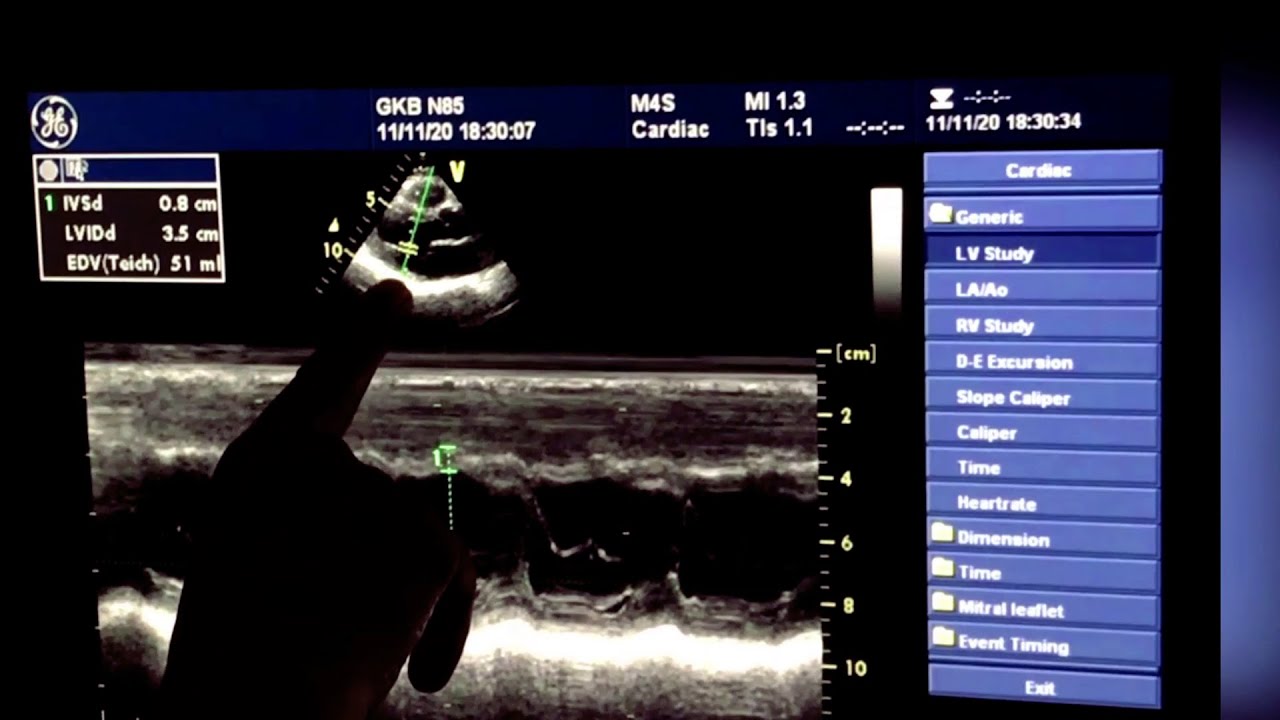

УЗИ сердца в  4d, стрейн эхо.

Значительная дилатация левого предсердия,LAVI 49 ml/m2. Вероятно обусловлено аритмией. Незначительная дилатация корня аорты. Систолическая, диастолическая функции в норме, гипертрофии , нарушения кинеза миокарда нет. На 20 минуте - УЗИ сердца в 4d, стрейн эхо.